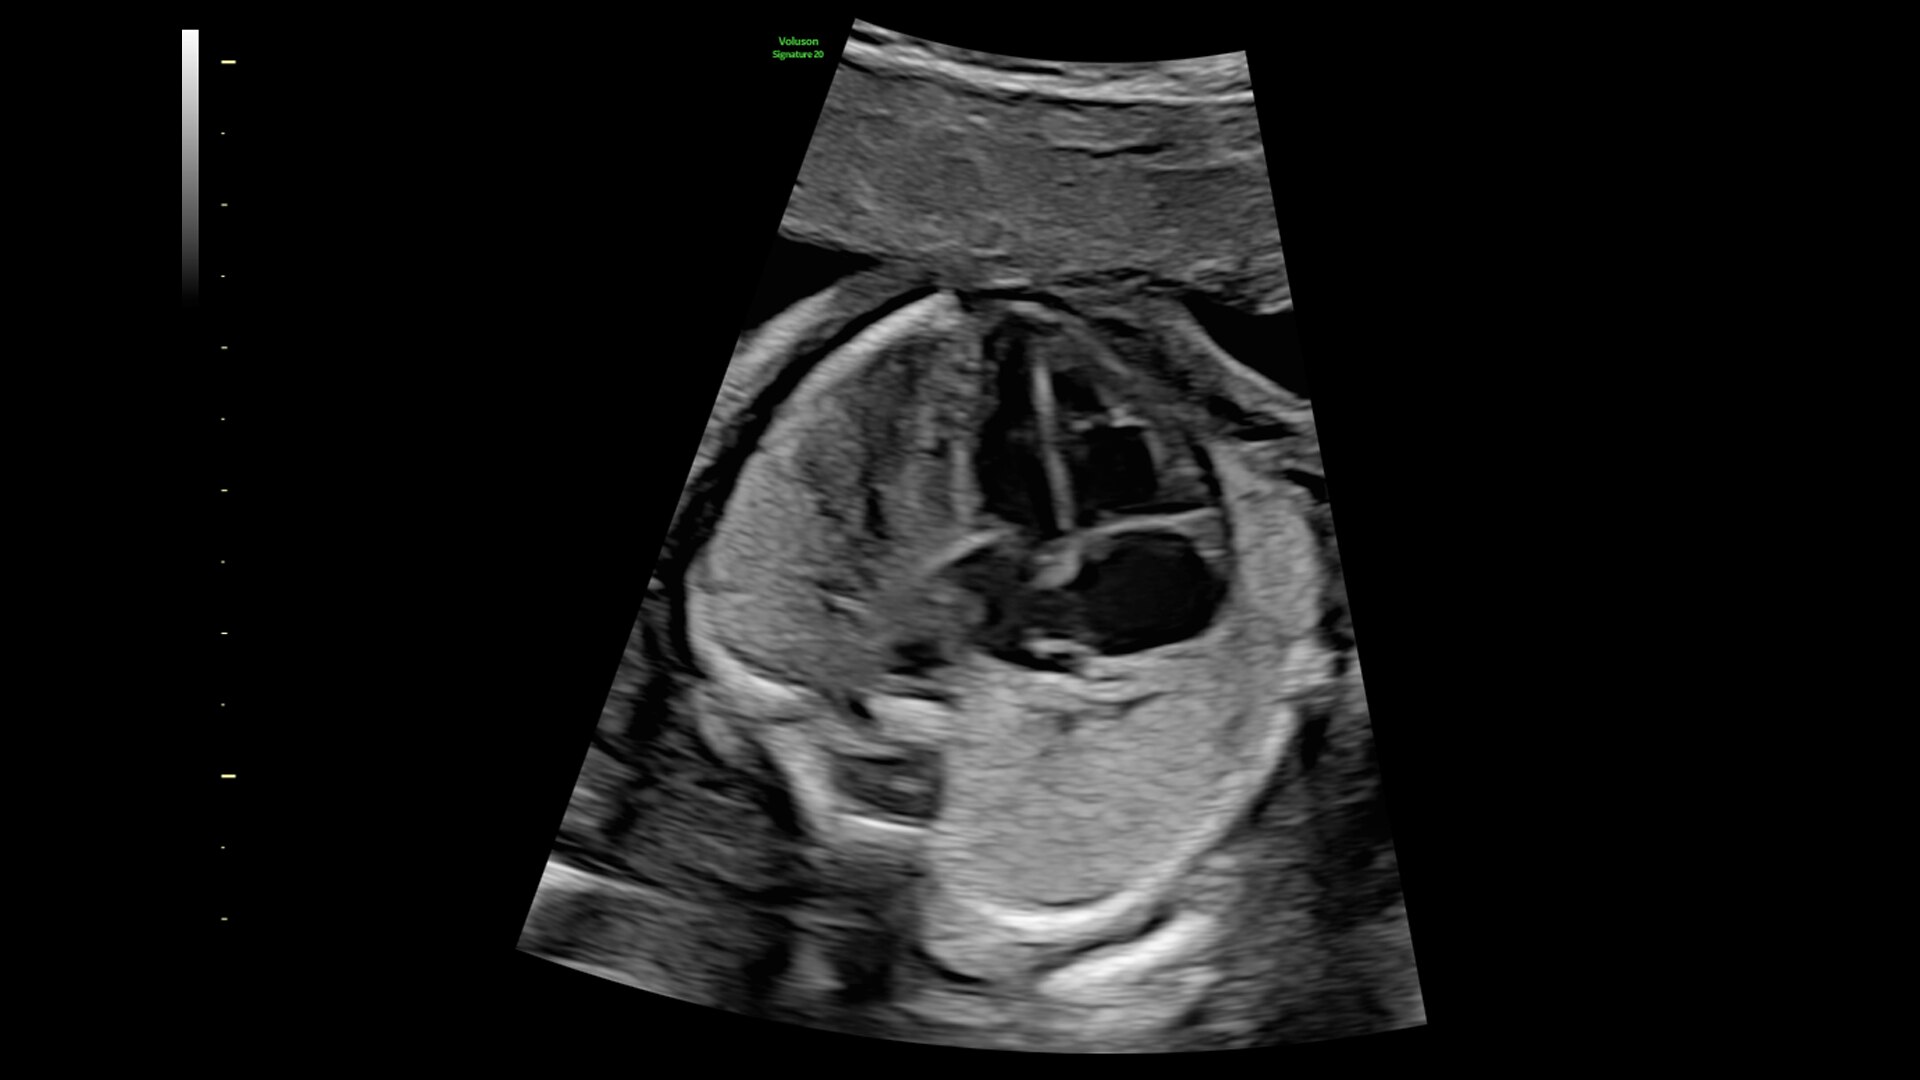

Advanced beamforming capabilities work in harmony with expert-level probes to deliver faster processing speeds and frame rates for enhanced detail and contrast resolution, greater color quality and sensitivity, and exceptional 3D/4D.

Advanced XDclear™ probe technology

For your most challenging patients

For your most challenging, technically difficult patients, our XDclear single-crystal technology probes allow you to achieve exceptional tissue and detail resolution while maintaining excellent penetration for a more robust, uniform image.